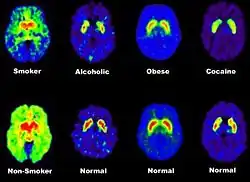

The greatest benefit of PET scanning is that different compounds can show flow and oxygen, and glucose metabolism in the tissues of the working brain. These measurements reflect the amount of brain activity in the various regions of the brain and allow us to learn more about how the brain works. PET scans were superior to all other metabolic imaging methods in terms of resolution and speed of completion (as little as 30 seconds), when they first became available. The improved resolution permitted better study to be made as to the area of the brain activated by a particular task. The biggest drawback of PET scanning is that because the radioactivity decays rapidly, it is limited to monitoring short tasks.[1]: 60

PET scanning is also used for diagnosis of brain disease, most notably because brain tumors, strokes, and neurondegenerative diseases (such as Alzheimer's disease and Parkinson's disease) all cause great changes in brain metabolism, which in turn causes detectable changes in PET scans. PET is probably most useful in early cases of certain dementias (with classic examples being Alzheimer's disease and Pick's disease) where the early damage is too diffuse and makes too little difference in brain volume and gross structure to change CT and standard MRI images enough to be able to reliably differentiate it from the "normal" range of cortical atrophy which occurs with aging (in many but not all) persons, and which does not cause clinical dementia.